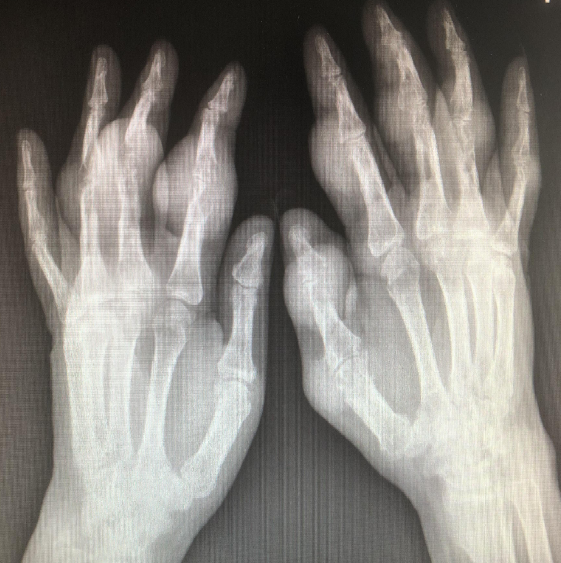

2021年6月2日大交班晨会病区部分病例分享如下: 病例1:男性患者,62岁,因“右拇指红肿痛破溃2天”入院。患者有高血压病史20余年、“痛风”病史10余年。入院诊断:右拇指痛风性溃疡、双手多发性痛风性结节、左手1-5指右手示中环指痛风性关节炎、双足多发痛风性结节、双足趾痛风性关节炎......。

(患者双手多发痛风结节)

入院后给予痛风石清理术、清创缝合术,术后切口顺利愈合。

四病区周小洋主任进一步对患者病情进行了介绍。该患者的双手、双足多发痛风结节,并且已经发展到韧带严重受损。即使手术后,功能也很难恢复。该病例说明,目前全社会对于糖尿病、高血压的防治、宣教工作做得不错,患者普遍接受了需要长期、终身治疗以预防并发症的理念。但是痛风的防治、宣教工作还做得不够。许多患者认为,“痛风”就是急性“关节炎”,不痛就不需要治疗,最终以至于发展到关节、韧带严重受损,甚至脏器功能严重损害。 周主任又详细介绍了痛风石清理术的操作细节,进一步阐述了该类手术容易手术切口不愈合的风险,及造成不愈合的可能原因、操作注意事项。